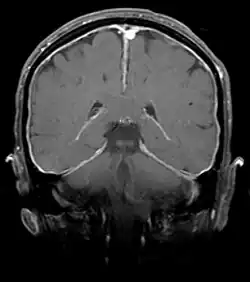

Differenzialdiagnostisch muss eine bakterielle Meningitis anhand klinischer Zeichen (Fieber, meningeale Reizzeichen) und im Zweifelsfall durch weiterführende Diagnostik (Erregernachweis durch erneute diagnostische Liquorentnahme, Magnetresonanztomografie-Aufnahmen) ausgeschlossen werden. Weitere mögliche Ursachen eines akut aufgetretenen Kopfschmerzes sind eine aseptische Meningitis und Raumforderungen innerhalb der Schädelhöhle wie etwa Hirnblutungen.[2]